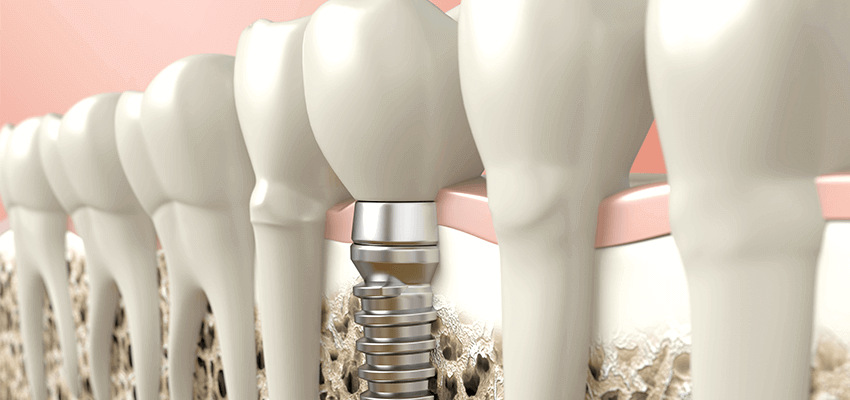

Nossa estrutura óssea está sempre em processo de formação e reabsorção, em um estado de equilíbrio dinâmico. Quando perdemos um dente, iniciam-se algumas alterações que resultam no desequilíbrio desse sistema, levando a reabsorção ou à atresia do osso alveolar.

A reabsorção óssea alveolar pode ser ocasionada por fatores como a perda precoce dos dentes, próteses removíveis, traumas, extrações dentárias e doenças periodontais. Isso interfere na reabilitação oral por meio de implantes, comprometendo assim o posicionamento correto dos dentes, a estética, a biomecânica e a funcionalidade dos dentes.

Muitos pacientes que tem indicação para a reabilitação com implantes deverão se submeter a algum procedimento reconstrutivo ósseo para sua correta instalação. Os enxertos podem ser realizados no momento da remoção do dente, antes da instalação dos implantes ou simultaneamente.